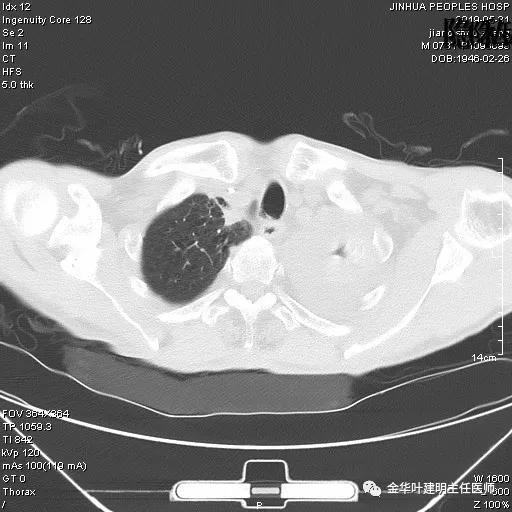

患者,男性,73岁,金华人。因“咳嗽咳痰伴胸闷2月,检查确诊左肺癌1周”入院。气管镜: 气管支气管内较多脓性分泌物,左肺上叶前段管腔新生物,局部活检、毛刷。气管镜病理:(左肺活检)鳞癌。阅胸部CT见左上叶开口处新生物,斟酌需左上叶袖式切除及淋巴结清扫。具体CT表现如下:

斟酌左侧大量胸腔积液,遂进一步胸部CT检查:

以上是肺窗表现,下面为纵隔窗影像: